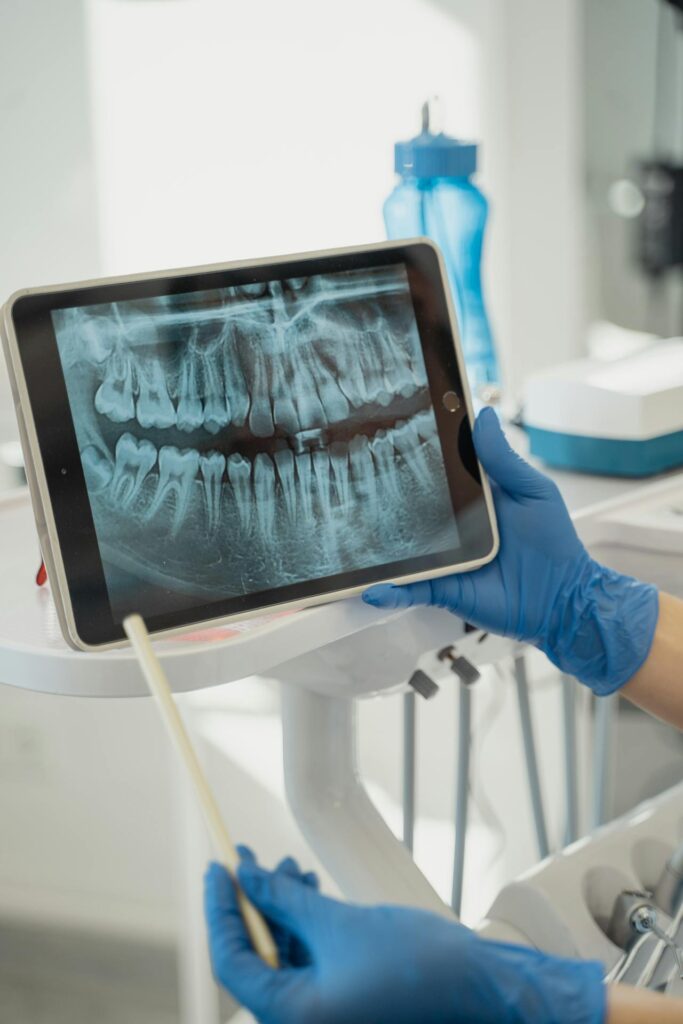

Diş röntgeni diş, çene kemikleri ve diş eti seviyesinin klinik muayenede görülmeyen kısımları hakkında fikir edinmek amacıyla X ışını yardımıyla elde edilen radyolojik görüntülerin adıdır. Diş röntgenleri tedaviye başlanmadan önce teşhis, tanı ve planlama amaçlı istenebileceği gibi, tedavi süresince ve tedavi sonrasında kontrol amaçlı olarak da istenebilmektedir.